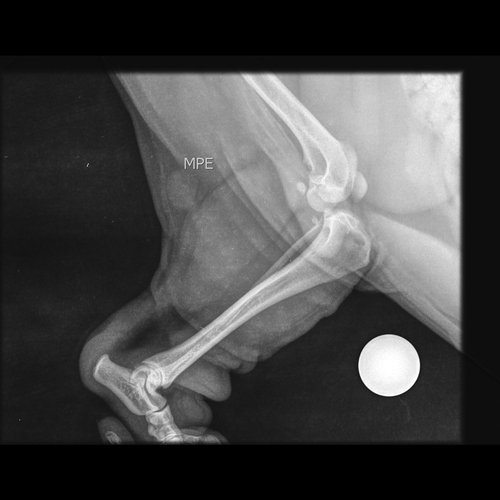

Meu nome é Gedilson, estou fazendo esta vaquinha para fazer a cirurgia do Thor (Lhasa Apso) que pulou da cadeira e teve uma fratura na perna esquerda traseira (exames abaixo). no hospital público aqui de Santo André não foi possível fazer pois não tinham as ferramentas necessárias que segundo eles custam 18 mil reais.

Então vamos ter que fazer a cirurgia dele em até 30 dias para não afetar a outra perna e coluna.

Este valor será para pagar a cirurgia e os remédios necessários para a recuperação dele, quem puder ajudar que Deus abençoe muito!